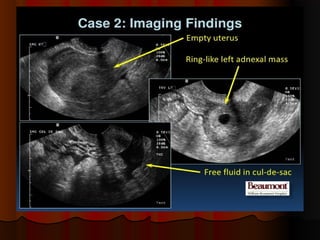

The above ultrasound and color Doppler images show the

lower margin of the placenta partially covering the internal

os, suggesting

os, suggesting partial placenta previa

partial placenta previa

.